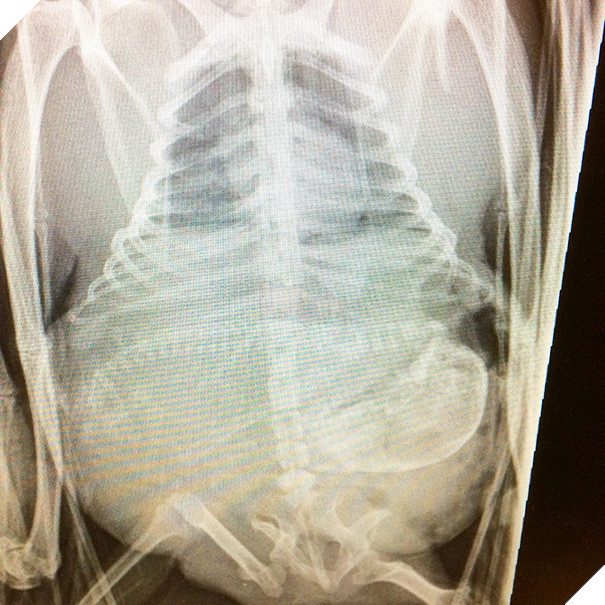

Trông có vẻ như các bé cún rất đông mà bụng chó mẹ thì lại chật hẹp. Thời gian thai của những chú cún hình thành và làm tổ ở sừng tử cung cho tới khi ra đời là khoảng 58 - 68 ngày (trung bình là 9 tuần). Những chú chó càng ít thai (dưới 4 con) thì thời gian mang thai càng dài.